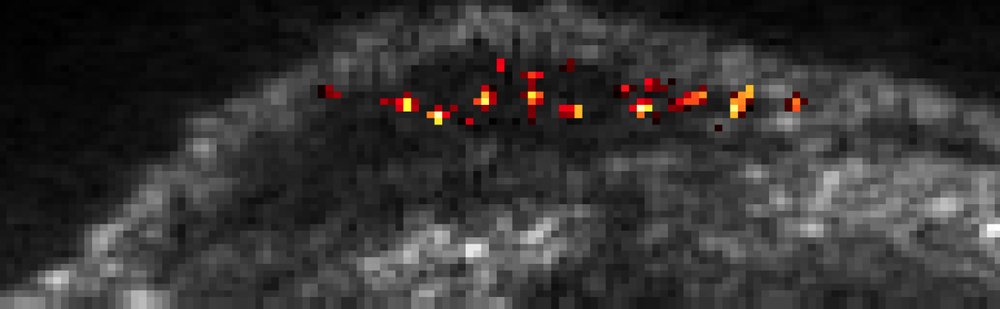

That blip is so clear that it can easily be detected by the researchers, even amid all the background noise produced by ultrasound penetrating through tissue. Shapiro says recent work on engineered strains of injectable bacteria that attack cancer cells, or "tumor-homing" bacteria, creates a need for better ways to track these cells to see where in the body they land. The researchers showed that when the bacteria were also engineered to carry the gas-vesicle gene, it was possible to track individual bacterial cells as they entered and traveled through the liver after being injected into the bloodstream.